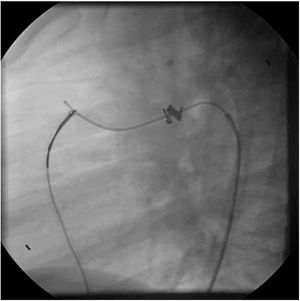

An early post-procedure complication rate of 1.8% was found (four patients). Three patients presented isolated loss of arterial pulse and were successfully treated with fibrinolytics. The most severe complication was in a seven month-old patient who presented device embolization 48 hours after the procedure. In this infant with a history of prematurity (born at 26 weeks of gestation), an Amplatzer duct occluder II Additional Sizes (5x6 mm) had been implanted. Loss of lower limb arterial pulse was noted a few hours after the procedure. A vascular doppler ultrasound confirmed occlusion of the femoral artery and thrombolysis with recombinant tissue plasminogen activator was started. After 48 hours, a chest radiograph revealed the device had migrated (Figure 13), with computed tomography confirming the device was at an inferior lobar branch of the left pulmonary artery. This required urgent surgical removal of the Amplatzer duct occluder II Additional Sizes and PDA ligation, which were both uneventful.